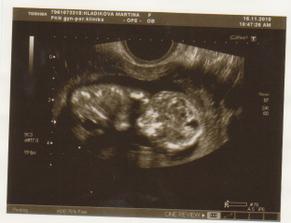

NT screening 12+4tt

1. velké měřeníčko